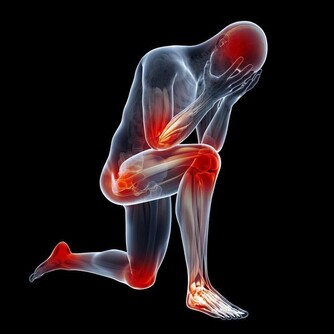

包括胃癌、腸癌、肺癌等的大多數癌症,都會帶來一些共同的症狀,比如體重減輕、疲倦、虛弱等,然而根據腫瘤生長部位的差異,每種癌症也有它自己獨特的信號。

只不過,這個信號不一定那麼典型那麼明確,有時候會讓你忽視,有時候會讓你找錯方向。現在,就讓我們來看看那些常見癌症通常都有哪些較為特別的跡象。